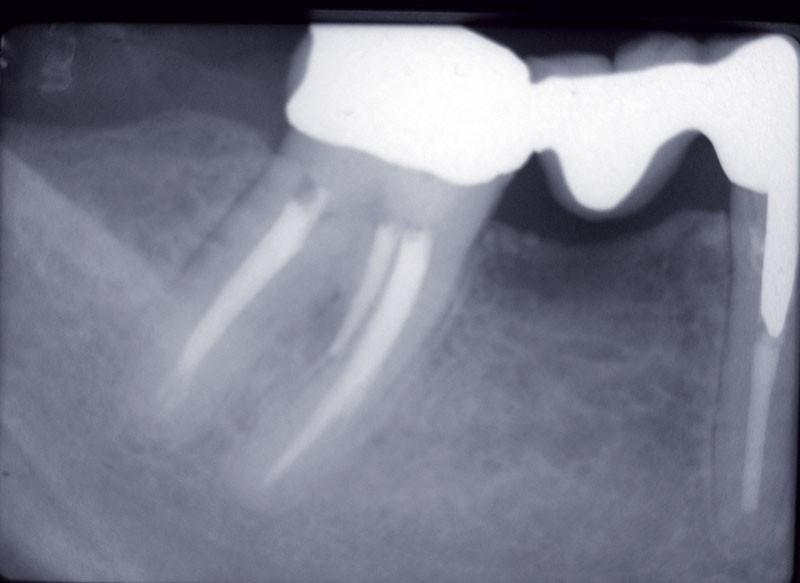

Dans la partie II (1er avril 2015), nous avons vu que le traitement local est primordial pour combattre l’infection endodontique.

Nous avons vu que, à l’exception de quelques rares cas spécifiques, dans la plupart des situations cliniques, la prescription des antibiotiques adjuvants est injustifiée.